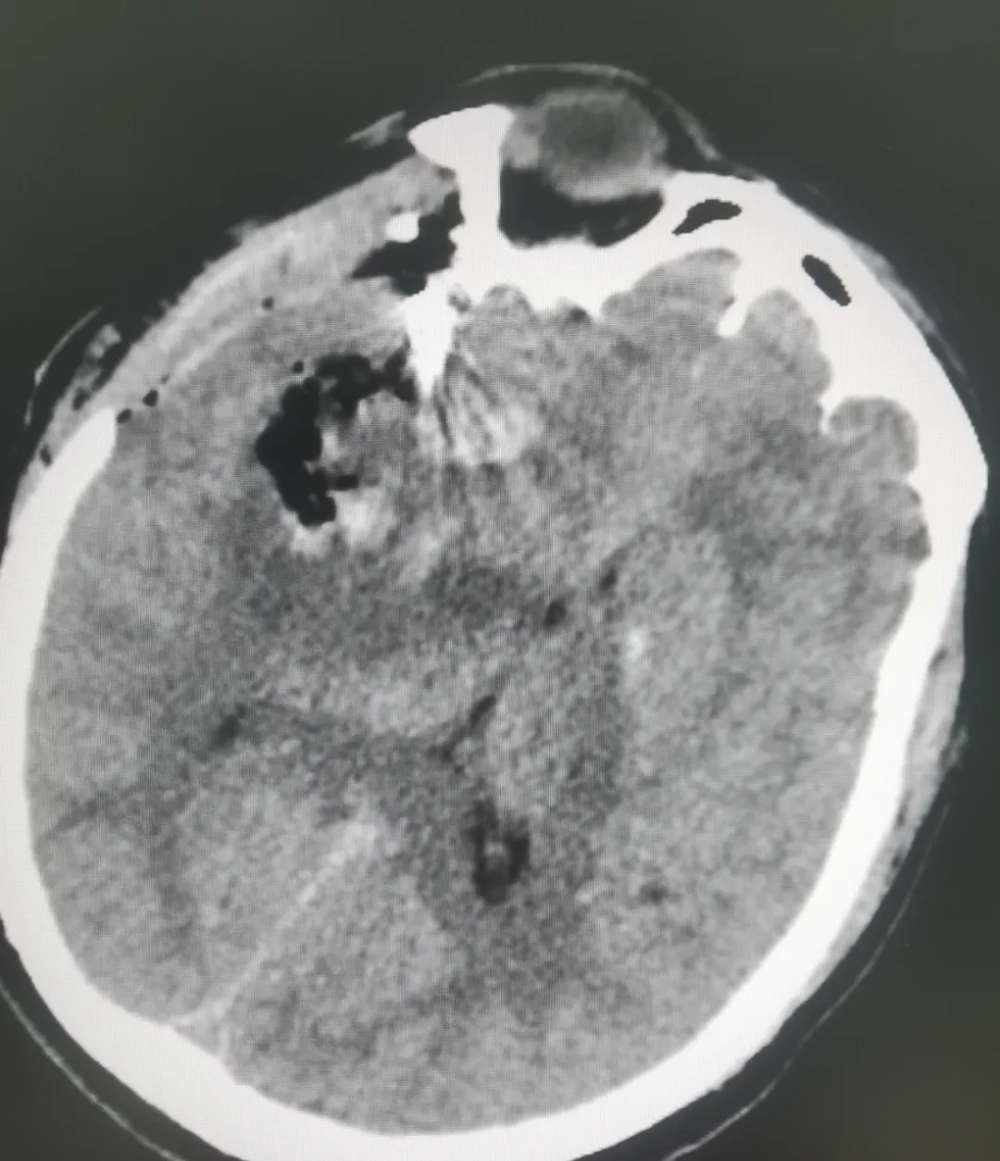

【填補縣域空(kōng)白】武寧縣總(zǒng)醫院人民醫院院區神經外科成功完成首例腦(nǎo)動脈瘤夾閉手術

近日,武寧縣總醫院(yuàn)人民醫院院區神(shén)經外科團隊順利完成了我縣首例破裂腦動脈瘤夾閉手術,患者術後情況良好,恢複(fù)效果理想。

腦動脈瘤夾閉借助高清晰顯微鏡下操作,手術難度高、風險大,以(yǐ)往(wǎng)此類患者隻能轉診(zhěn)上級醫院。人民醫院(yuàn)院區神經(jīng)外科團隊憑借紮實的(de)專業功底迎難而(ér)上,精準操作,成功拆除患者顱內"不定(dìng)時炸彈(dàn)"。這一突破填補了我縣(xiàn)在腦動脈瘤治療領域的技術(shù)空白。

近年(nián)來(lái),武寧(níng)縣總醫(yī)院人民醫院院區(qū)神經外科團隊借力與湘雅醫院江西醫(yī)院緊(jǐn)密(mì)型醫聯體東風(fēng),展現出蓬勃向上的發展勢頭,多項高難度診療技術日臻成熟:微創神經內鏡技術、顯微(wēi)鏡下腦內血腫(zhǒng)清除術、腦膜瘤切除術以及複雜重型顱腦創傷救治能力實(shí)現突破性(xìng)提升。此次腦動脈瘤夾閉手術成功實施,在縣域神經(jīng)外科(kē)領域(yù)書寫了新(xīn)的篇章,實現了“零”的突破。